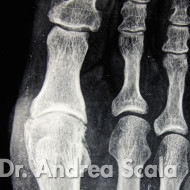

IMG 1 – La radiografia mostra un alluce rigido in fase iniziale.